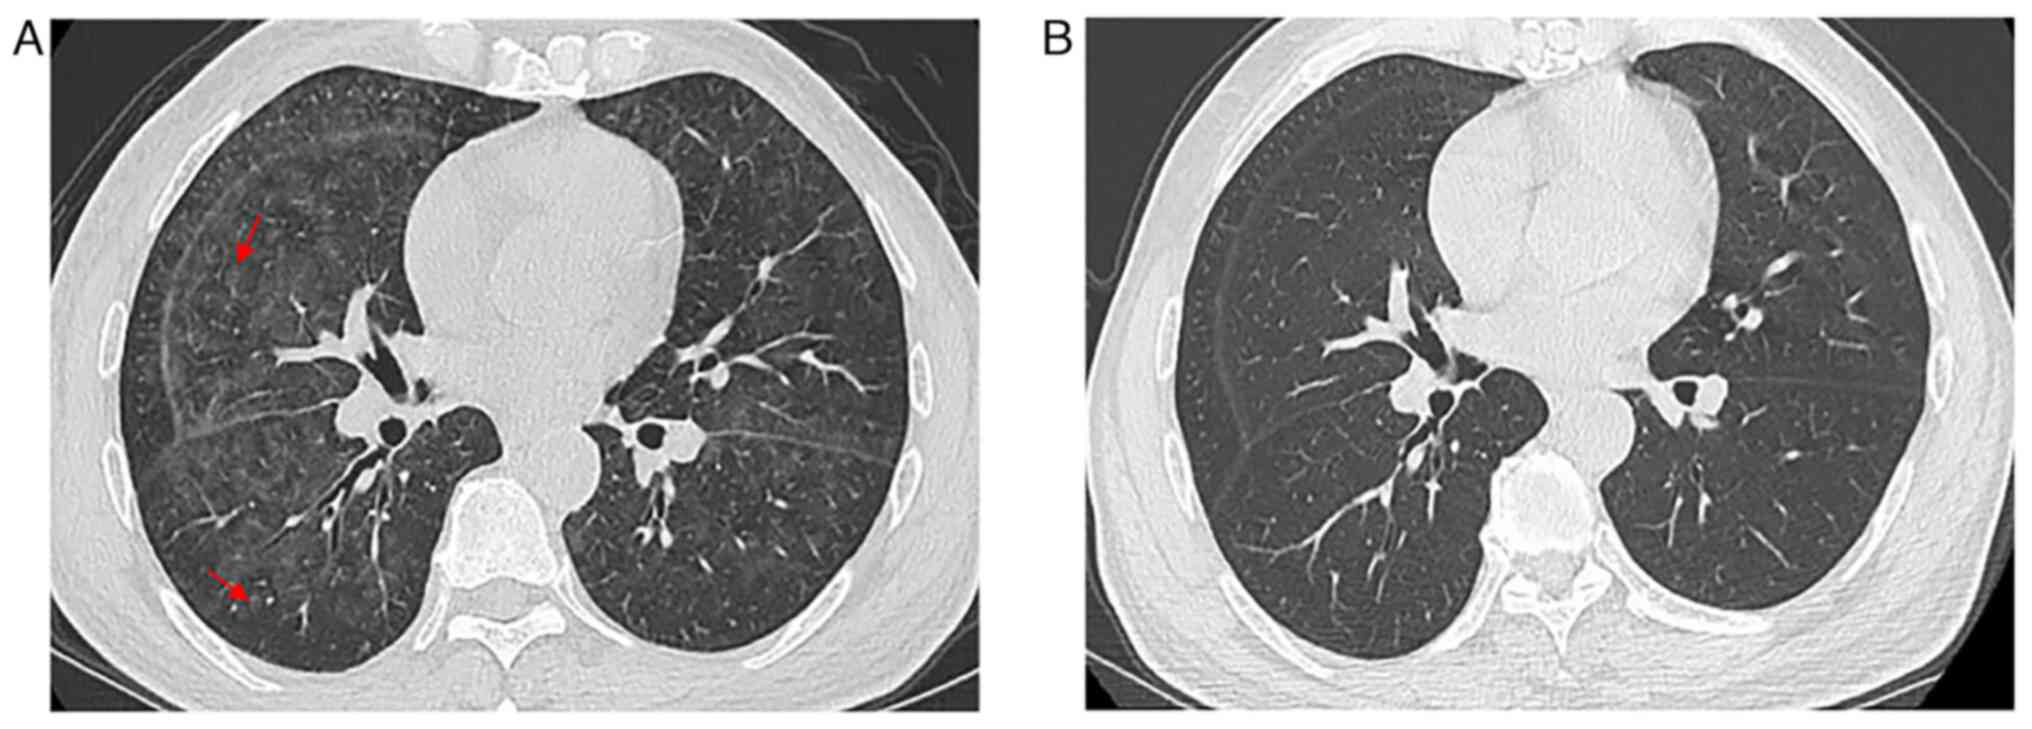

Case 3

A 65-year-old male patient was admitted to Nanjing Drum Tower Hospital in March 2017 with a 3-month history of progressive dyspnea and cough. The patient had no prior history of lung disease, chest pain, intermittent fever or night sweating. No focal findings were noted on physical examination, especially of the skin and central nervous system, and lymph nodes were not palpable. A CT examination revealed diffuse ground-glass attenuation and thickened interlobular septa in the upper lungs (Fig. 3A and B). No abnormal soft tissue mass was observed in the mediastinum, bilateral hilus and axilla. Whole-body positron emission tomography-computed tomography (PET-CT) scan revealed only mild 18F-fluorodeoxyglucose (FDG) uptake in both lungs. The patient was mistakenly diagnosed with pneumonia and received wide-spectrum antibiotics treatment (2 g cefazoxime sodium, twice per day) for half a month. The patient's symptoms continued, and the treatment had no effect. The patient was discharged from hospital after diagnosis of IVLBCL using TBLB and did not return for follow-up treatment and examination.

Figure 3.

Case 3. (A) Axial computed tomography slice of the chest showed diffused ground-glass attenuation. (B) Coronal images demonstrate predominant distribution in the upper lobes of bilateral lungs.

Compared with other pulmonary lymphoma, IVLBCL generally does not involve lymphadenopathy or a localizing solid mass, as the lymphomatous cells mainly involve the pulmonary arteries and capillary beds (14). Results of CT assessments are diverse and can be inconspicuous or show GGO and interstitial infiltration (11,12,14). In the cases of the present study, patchy areas of GGO existed on patient presentation and this accentuated the bilateral lung attenuation resulting from pulmonary vascular obstruction. In case 1, the chest HRCT revealed bilateral disease that was pneumonia-like, which progressed partly to consolidation. Due to local interlobular septal thickening along with the thickening of bronchovascular bundles, new GGO indicated lymphatic and hematological spread. The other 3 cases showed bilateral GGOs, micronodules and thickened interlobular septa in the lungs without pleural involvement, which suggested that the disease may spread along lymphatic structures. In case 2, the pulmonary shadows completely disappeared after a short-term chemotherapy schedule, which supported the diagnosis of IVLBCL. The etiology of GGO (heterogeneous and partially consolidated) in all four patients remains unclear. Malignant cells may invade the alveolar space, resulting in consolidation (increased density) on CT imaging. Increased diffuse density in bilateral lungs with GGOs and thickening of interstitial septum needs to be distinguished from non-neoplastic lesions, such as interstitial diseases and mechanical pneumonia, which may also present as progressive dyspnea with cough and other manifestations of obstructive ventilation. TBLB and bronchoalveolar lavage fluid can be used to aid diagnosis. Undoubtably, IVLBCL needs to be differentiated from venous thromboembolism and other intravascular malignancies of the lung, including lymphomatoid granulomatosis, angiocentric lymphoma and pulmonary involvement by acute and chronic lymphocytic leukemias (3). At this point of the patient examination, the clinical manifestations and CT characteristics may be non-specific, and immunohistochemistry will provide great help for the correct diagnosis.